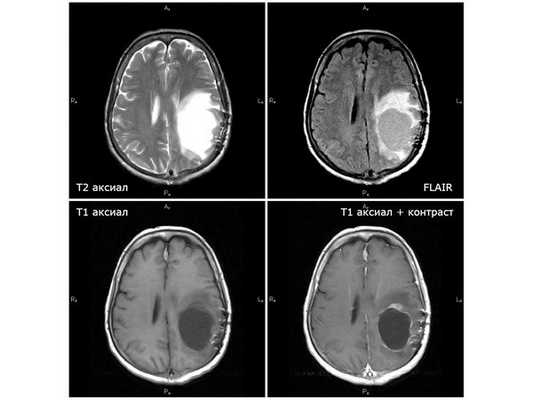

МРТ от 21.11.18 (через 7 недель после первого этапа химиолучевой терапии): единственный случай положительной динамики

НАЧАЛО ЛЕЧЕНИЯ На базе нейрохирургического отделение больницы с 11.08.18 по 25.08.18 была проведена противоотёчная и симптоматическая терапия. По результатам ЭЭГ (электроэнцефалографии) от 13.08.18, признаков пароксизмальной активности (ухудшения) на момент исследования нет. Чтобы решить вопрос об оперативном лечении, 25.08.18 пациентку направили на консультацию нейрохирурга в областную клиническую больницу Белгорода. Оттуда её госпитализировали в московский центре нейрохирургии им. ак. Н.Н.Бурденко. Там пациентка находилась на стационарном лечении с 29.08.18 по 04.09.18. 30.08.18 национальном медицинском центре ей провели операцию: удалили внутримозговую опухоль левой теменной доли с использованием УЗ-навигации и нейрофизиологического мониторинга проводящих путей. Исследования опухолевой ткани показали, что удалённая опухоль является глиобластомой — высокозлокачественной астроцитарной опухолью без выявленной мутации IDH1 R132H. По результатам послеоперационной КТ без контрастирования, ишемических и геморрагических осложнений не выявлено, остатки опухоли не обнаружены. Послеоперационный период протекал удовлетворительно. На следующий день пациентка уже могла находиться в вертикальном положении, сила в правых конечностях увеличилась, что говорило о положительной динамике. Пациентке было рекомендовано наблюдаться у невролога, онколога и сосудистого хирурга по месту жительства, проконсультироваться с радиологом и химиотерапевтом центра нейрохирургии. Учитывая природу опухоли, клиническую картину и данные исследований, женщине рекомендовано пройти курс лучевой терапии. Начинать его можно было в течение 1-4 недель после проведённой операции. ХИМИОЛУЧЕВАЯ ТЕРАПИЯ: рекомендации Лечение было комбинированным: радиотерапия на ложе опухоли до суммарной дозы (СОД) 60 гр с одновременным приёмом темозоломида в дозе 75 мг/кв. м. Рекомендуемая доза препарата на весь период лучевой терапии — 120 мг/сут. Темозоломид показано принимать внутрь натощак за два часа до приёма пищи, запивая водой (в дни проведения радиотерапии — за 0,5-1,5 часа до сеанса), по одной капсуле 100 мг и одной капсуле 20 мг либо 100 мг/сут ежедневно без перерыва на выходные. При возникновении тошноты на фоне лечения рекомендовано за 30 минут до приёма темозоломида натощак принимать 4 мг ондансетрона. Через три недели после завершения радиотерапии требуется выполнить МРТ с контрастированием и повторно проконсультироваться в центре нейрохирургии им. Н.Н. Бурденко для дальнейшего плана химиотерапии. Следующий этап химиотерапии планируется продолжить через 28 дней после завершения комбинированного лечения. При стабильной картине МРТ и удовлетворительных показателях крови приём темозоломида в дозе 200 мг/кв. м нужно будет продолжить в другом режиме: рекомендуемая доза — 300 мг, принимать ежедневно внутрь в течение пяти дней с последующим перерывом в 23 дня. В целом запланировано 6-10 курсов химиотерапии с дальнейшим решением вопроса о необходимости продолжения лечения. НАЧАЛО ХИМИОЛУЧЕВОЙ ТЕРАПИИ Первый этап химио- и радиотерапии проводился на базе Белгородского онкологического диспансера около месяца — с 19.09.18 по 12.10.18. Лечение предполагало лучевую терапию с суммарной лучевой дозой 30 гр. на фоне приёма 100 мг темозоломида за час до сеанса облучения. В результате лечения состояние пациентки стабилизировалось, неврологический статус не страдал. Лучевые реакции выражены умеренно. Рекомендовано: ⠀•⠀наблюдаться у онколога и невропатолога; ⠀•⠀при необходимости пройти противоотёчную терапию; ⠀•⠀ограничить физические и эмоциональные нагрузки; ⠀•⠀через три недели при отсутствии противопоказаний продолжить лучевую терапию с госпитализацией в Белгородский онкологический диспансер. Через две недели после химиолучеовй терапии 30.10.2018 проведено контрольная МРТ: снимки показали феномен псевдопрогрессии с увеличением поперечной дислокации и нарастанием отёка вокруг опухоли. Примерно через месяц после завершения первого этапа лучевой терапии усилились головные боли и стала нарастать общая слабость. В связи с этим с 06.11.18 по 16.11.18 пациентка находилась на стационарном лечении в нейрохирургическом отделении городской больницы № 1 г. Старый Оскол. Получала осмотерапию, лёгкую дегидратацию, кортикостероидные и гастропротективные (противоязвенные) препараты. Выписана в удовлетворительном состоянии. Рекомендовано принимать дексаметазон по 25 мг три раза в день. Спустя семь недель после химиолучевой терапии 21.11.18 проведена ещё одна контрольная МРТ: наблюдается положительная динамика с уменьшением объёма опухоли, поперечной дислокации и отёка вокруг опухоли. ВТОРОЙ ЭТАП ХИМИОЛУЧЕВОЙ ТЕРАПИИ Для проведения второго этапа лучевой терапии пациентка госпитализировалась в Белгородский онкологический диспансер. Там она находилась с 26.11.18 по 14.12.18. Проведена лучевая терапия на ложе опухоли головного мозга с суммарной очаговой дозой 30 гр. Общая суммарная доза за второй этап составила 60 гр. Ежедневно перед сеансом облучения пациентка принимала 100 мг темозоломида. Рекомендовано: ⠀•⠀наблюдаться и проходить лечение у онколога и невролога по месту жительства; ⠀•⠀прийти на контрольный осмотр в поликлинику Белгородского онкологического диспансера через два месяца.